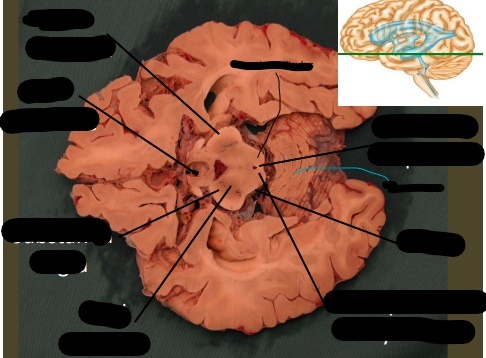

lable, note important features

uncus is seen on the ventral (inferior) surface of cerebram, pointing towards the mamillary bodies or optic chiasm. following the uncus, the change in the basic organization of cortex indicates the hippocampus